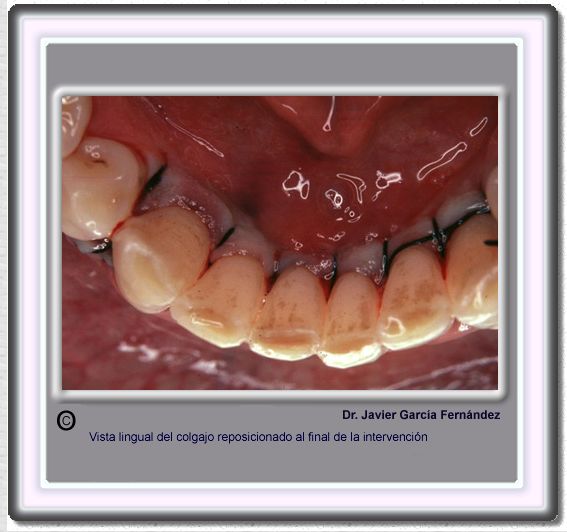

image 301